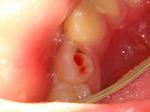

写真は12歳の男の子ですがやはり折れてしまい、感染根管処置を行わなくてはいけない例です。

折れたところが歯髄まで繋がっているため感染を起こしたもので、まだ根の先が成長しきっていないので成功率が低く根管治療を避けたいところですが仕方がありません。